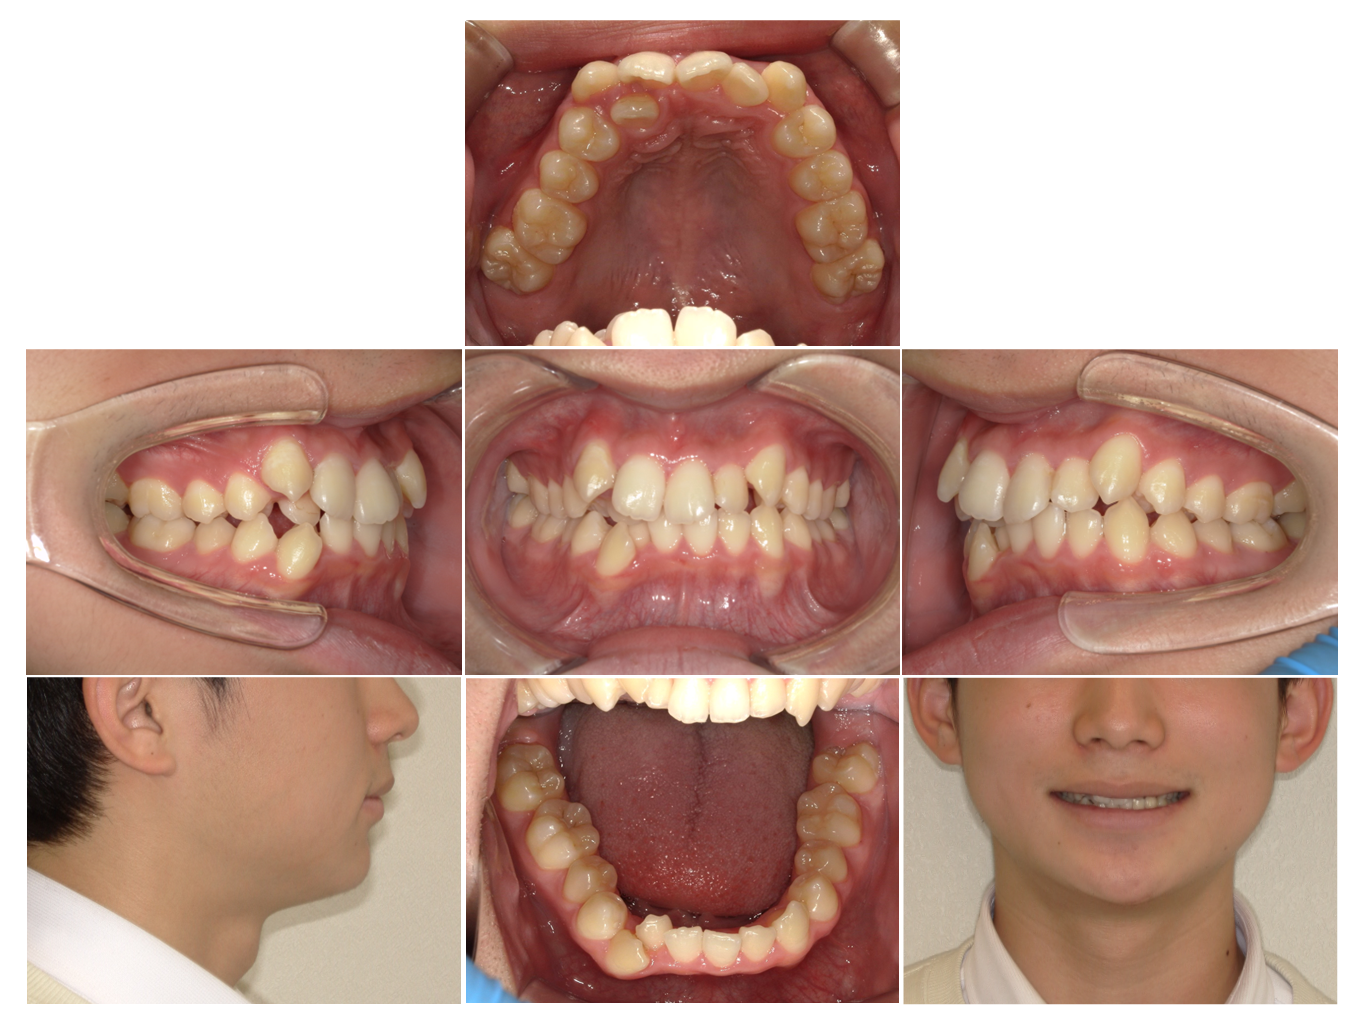

症例5

※画像をクリックすると拡大します。

| Before | After |

|---|---|

![]() |

| 項目 | 詳細 |

| 来院時の主訴 | 全体的なガタガタ |

| 医院での対応や適用装置 | 上顎の小臼歯抜歯、ワイヤー矯正にて主訴で |

| 通院期間 | 1年2ヶ月 |

| 通院回数 | 14回 |

| 治療費用総額 | 720,500円(学生割引適応) |

| リスクと副作用 | 矯正治療による歯の移動に伴う痛み、歯根吸収、虫歯 |